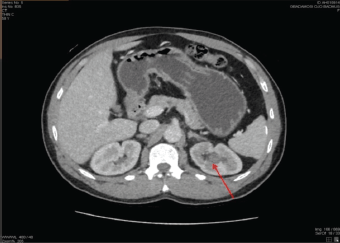

His physical examination showed a middle-aged man, in painful distress, afebrile, not pale and well hydrated. His abdominal examination revealed tenderness on the left flank, with no detected palpable mass. An Abdominopelvic ultrasound scan and computed tomography urography (CTU) initially detected no abnormality; while an abdominopelvic magnetic resonance imaging (MRI) (Figure 1) report was suggestive of a growth in the upper pole involving the collecting system of the left kidney. Following receipt of the abdominopelvic MRI report, a review of the CTU was done, which showed a focal, mildly enhancing tumour at the left upper pole calyx (Figure 2). The right kidney appeared normal on both CTU and abdominopelvic MRI (Figures 1 and 2).

Figure 2. A repeated contrast-enhanced CTU image (axial section) showing a focal, mildly enhancing tumour seen in the left upper pole calyx (red arrow).